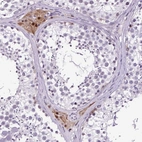

Immunohistochemical staining of human testis shows strong nuclear and cytoplasmic positivity in Leydig cells.